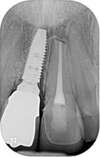

Il s'agit d'un cas d'une chute avec expulsion de l'incisive centrale droite et fracture de l'incisive centrale gauche.

Un implant avec greffe osseuse a été posé en site de l'incisive droite et une facette sur dent dévitalisée sur l'incisive gauche.

La réalisation a été faite par un laboratoire meilleur ouvrier de France.